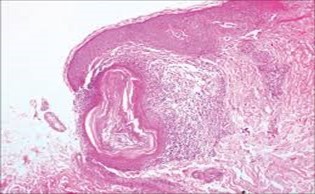

A cogent tissue specimen demonstrates typical features of comedones as follicular ostia distended and impacted with keratin. Significant histological manifestations are the occurrence of enlarged, grouped, distended follicular ostia demonstrating an absence of hair shafts along with impaction of laminated keratin. Base of the follicular invaginations may or may not delineate singular, rudimentary glandular structures. Miniature cysts, cystic invaginations and occasional enlarged cysts can be encountered. Cystic articulations are diverse and preponderantly layered by keratinizing, stratified squamous epithelium. Hyperkeratosis or epidermolytic hyperkeratosis and acanthosis of superimposed epidermis can concur although the lesion is devoid of parakeratosis or dyskeratosis5, 6.

Nevus comedonicus demonstrates immune reactivity to cytokeratin, simulating the expression of normal cutaneous surfaces. Generally encountered within the granular epidermal layer, immune reactivity for filaggrin is demonstrable within the entire epidermal thickness of closed comedones, a molecular which can be implicated in the genesis of nevus comedonicus6, 7. Electron microscopy demonstrates an enhanced quantification of Langerhans cells, numerous kerato-hyaline granules along with an abundance of tonofilaments within upper portion of stratum spinosum. Incompletely differentiated arrector pili muscles are impacted with intracellular glycogen particles6, 7. Figure 1, Figure 2, Figure 3, Figure 4, Figure 5, Figure 6, Figure 7, Figure 8, Figure 9, Figure 10.

Figure 3.Nevus comedonicus with aggregated follicular ostia, lamellated keratin, hyperkeratotic stratified squamous epithelial lining and an attenuated superimposed epithelium12.

Figure 4.Nevus comedonicus with distended follicular ostia, keratin accumulation, hyperkeratotic epithelial lining and intervening loose fibro-connective tissue13.

Figure 9.Nevus comedonicus exemplifying a dilated, plugged follicular ostium, keratinous flakes and a layer of stratified squamous epithelium17.

Figure 10.Nevus comedonicus depicting an impacted, distended follicular ostium, keratinous aggregation and a superimposed, acanthotic, hyperkeratotic, stratified squamous epithelium17.